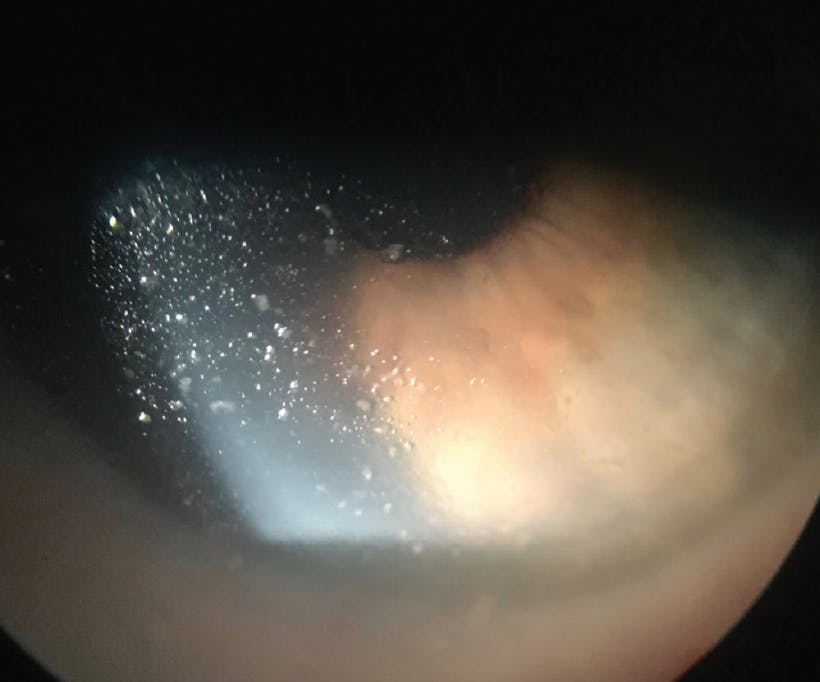

Patients who have OSD and other conditions such as ocular rosacea and meibomian gland dysfunction are susceptible to fogging of the anterior surface of the scleral lens. Those with exposure keratopathy after procedures such as ptosis repair, blepharoplasty, and injections of onabotulinumtoxin A (Botox, Allergan) and patients who have experienced a stroke or who have nerve palsy may not close their eyelid completely, resulting in a dry, exposed lens surface. Makeup and skin creams can also contribute to anterior scleral lens debris and fogging (Figure).